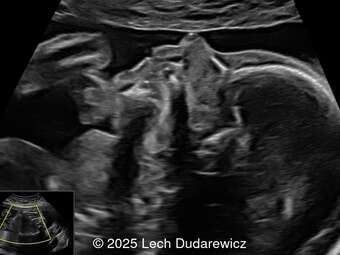

A 33-year-old nullipara with non-contributory medical history presented at 20 weeks, 6 days based on an early scan. Ultrasound revealed the following findings. There were no other apparent abnormalities. What is the most probable diagnosis?